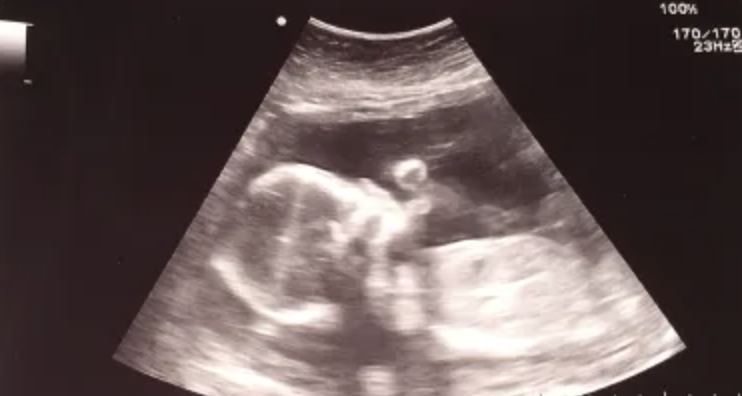

But the thing is...I'm now pregnant. 26 weeks to be exact. With this darling, sweet little angel GIRL!

You have to admit, she's already adorable, isn't she?